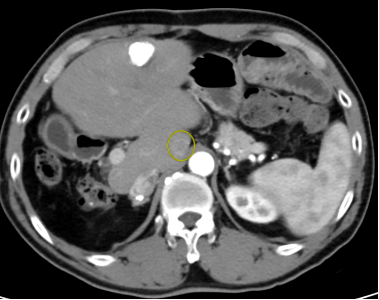

无水酒精消融术是在CT引导下,局麻后经皮穿刺进入一根细针,将针准确插入肝内肿瘤病灶中,并通过该针打入无水酒精。无水酒精进入肿瘤病灶后,使得肿瘤发生凝固性坏死,进而达到“毁损”肿瘤的目的。

图片

图为无水酒精消融穿刺针

图为术中经过穿刺针注入无水酒精治疗过程

图为术中精准将消融针穿刺进入肿瘤病灶并注射无水酒精